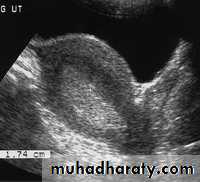

Endometrial hyperplasia. US image shows an endometrium with diffuse thickening (maximum thickness, 1.74 cm) due to hyperplasia (cursors). This finding was confirmed at biopsy.• Pathology of Endometrium